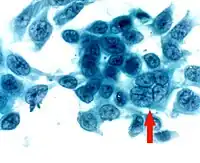

Impression cytology smear stained by Papanicolaou stain shows the presence of a multinucleated giant cell

A specific clinical diagnosis of HSV as the cause of dendritic keratitis can usually be made by ophthalmologists and optometrists based on the presence of characteristic clinical features. Diagnostic testing is seldom needed because of its classic clinical features and is not useful in stromal keratitis as there is usually no live virus. Laboratory tests are indicated in complicated cases when the clinical diagnosis is uncertain and in all cases of suspected neonatal herpes infection:[4][6]

• Corneal smears or impression cytology specimens can be analyzed by culture, antigen detection, or fluorescent antibody testing. Tzanck smear, i.e.Papanicolaou staining of corneal smears, show multinucleated giant cells and intranuclear inclusion bodies, however, the test is low in sensitivity and specificity.